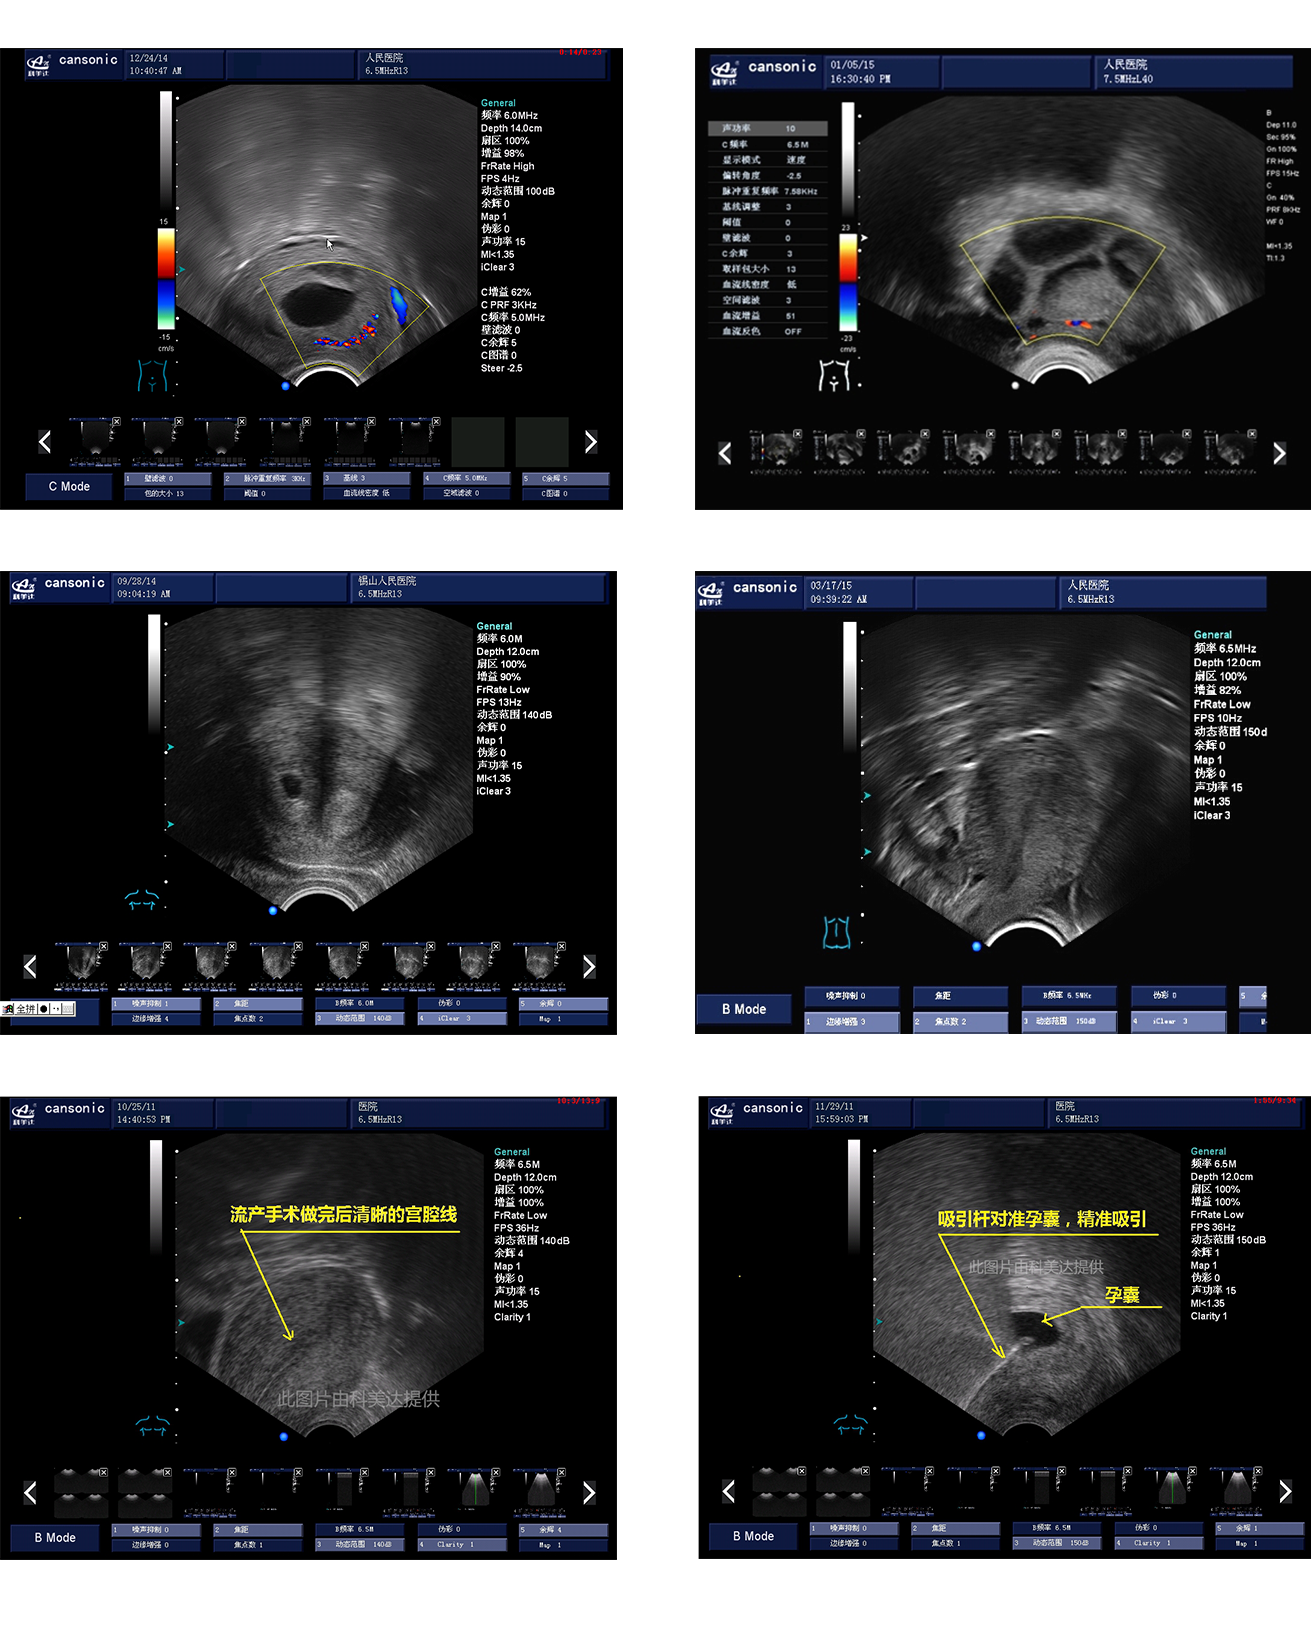

臨床圖示

1、薈萃前沿彩超技術(shù),使得超聲監(jiān)測(cè)與手術(shù)操作完美融合,實(shí)現(xiàn)宮腔手術(shù)的全程監(jiān)測(cè)

2、復(fù)合成像技術(shù),增強(qiáng)組織回聲,減少回聲失落,得到清晰、真實(shí)的手術(shù)影像

3、血流靈敏度高,清晰可見(jiàn)